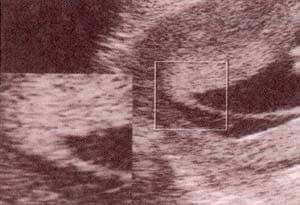

| fig. 53.– (a). gemelar bicorial – biamniótico. signo lambda. se establece precozmente el diagnóstico de corionicidad. en este caso se trata de un embarazo bicorial – biamniótico. | fig. 53.– (b). membrana interamniótica. obsérvese el grosor de la membrana correspondiente a un embarazo gemelar bicorial – biamniótico. |